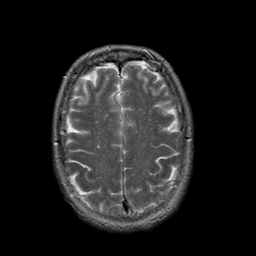

Stroke:T2-weighted MR #1 -- Slice #19

[Home][Help][Clinical] Slice 19